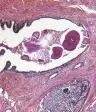

几乎所有的前列腺癌都被称为腺癌。这种类型的癌症在腺细胞中发育。而且,超过了10个前列腺癌中的九点腺泡的腺癌。它们影响一种称为Acini的细胞。